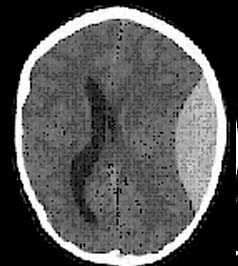

- определить степень сдавления или дислокации головного мозга объемным процессом,

- выявить наличие диффузного или перифокального отека и его степени,

- выявить внутрижелудочковую гематому,